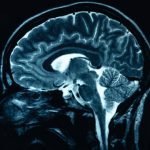

La liquirizia protegge il cervello dalla degenerazione

Le radici di liquirizia possono allearsi col cervello contro la degenerazione neurale. Consumandole, si potrebbe così diventare più resistenti a disturbi come Alzheimer o

Parkinson.